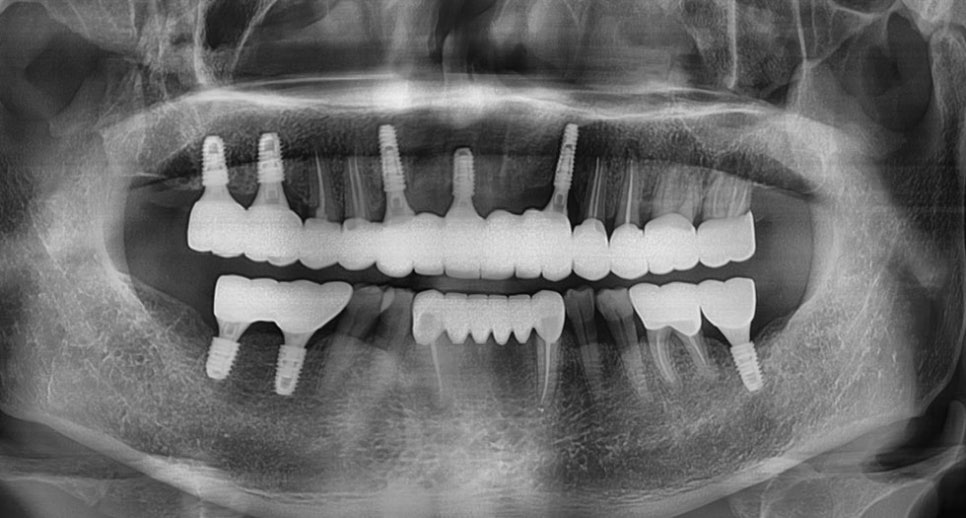

위 사진은 뉴엔임플란트센터에서의

CT 모의술식의 한 장면이며 미리 뼈와

기타 구조물들을 분석하여 임플란트 수술 전

다양한 상황을 예측하고 시뮬레이션 후

시행하고 있습니다.

이렇게 논현동임플란트치과 저희 뉴엔치과는 0.01mm의 오차도 허용하지 않는

최첨단 컴퓨터 분석, 3D 디지털 분석을

통해 명확한 위치에 임플란트가

식립될 수 있게 위치를 잡아주는 가이드

역할로 사람이 할 수 있는 아주 적은

오차도 용납하지 않고 꼼꼼히 수술합니다.